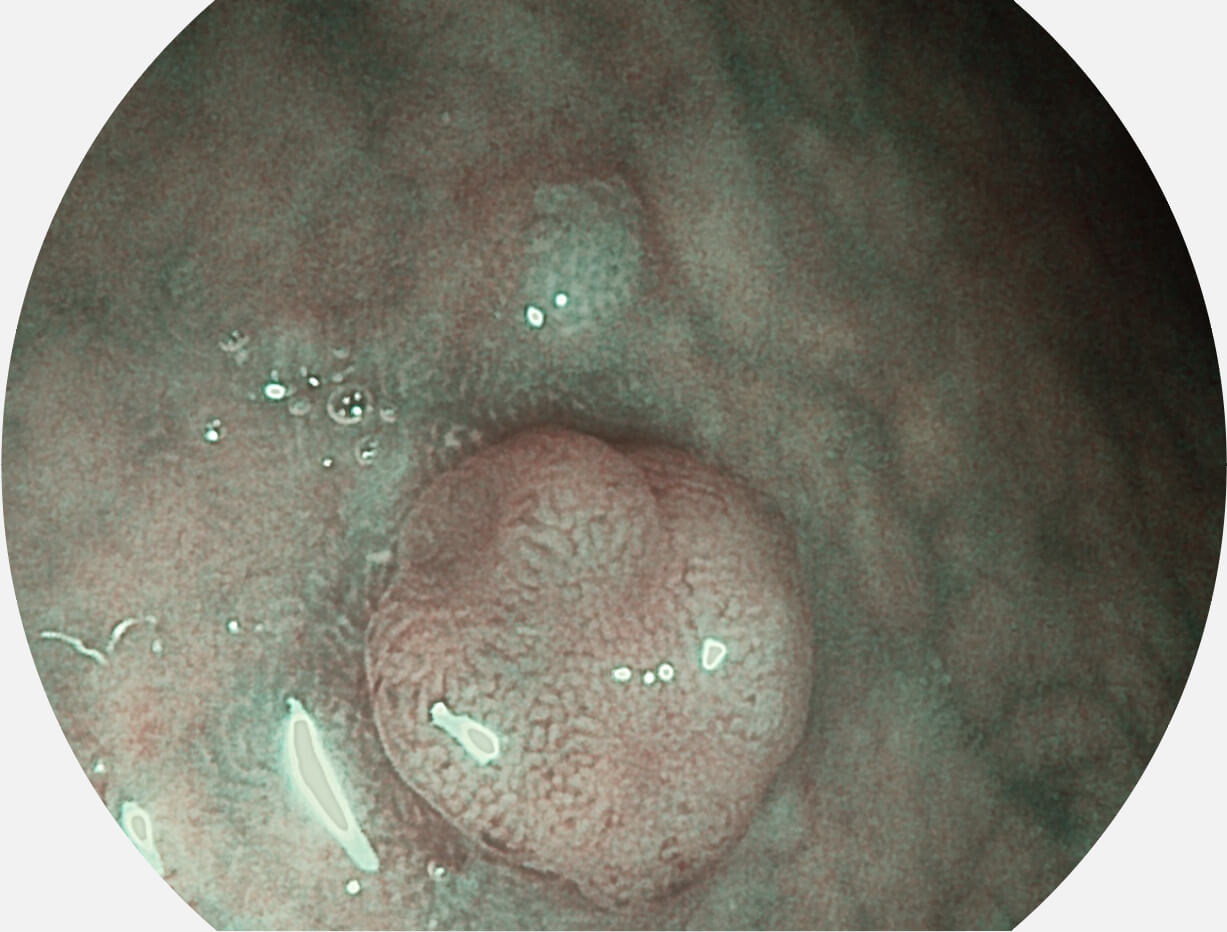

SFI图像

图像具有高亮度、高黏膜血管颜色对比度的特点,且不改变粘液、食物残渣、粪便的基本颜色,可在中远景下进行观察,助力消化道早期疾病的诊断。